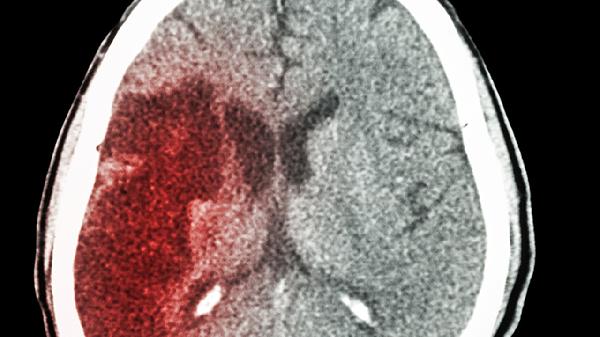

脑出血患者适合饮用清淡易消化、富含优质蛋白和维生素的汤类,主要有冬瓜排骨汤、鲫鱼豆腐汤、山药鸡汤、番茄牛肉汤、紫菜蛋花汤等。脑出血后胃肠功能较弱,需避免高盐、高脂及刺激性食材。